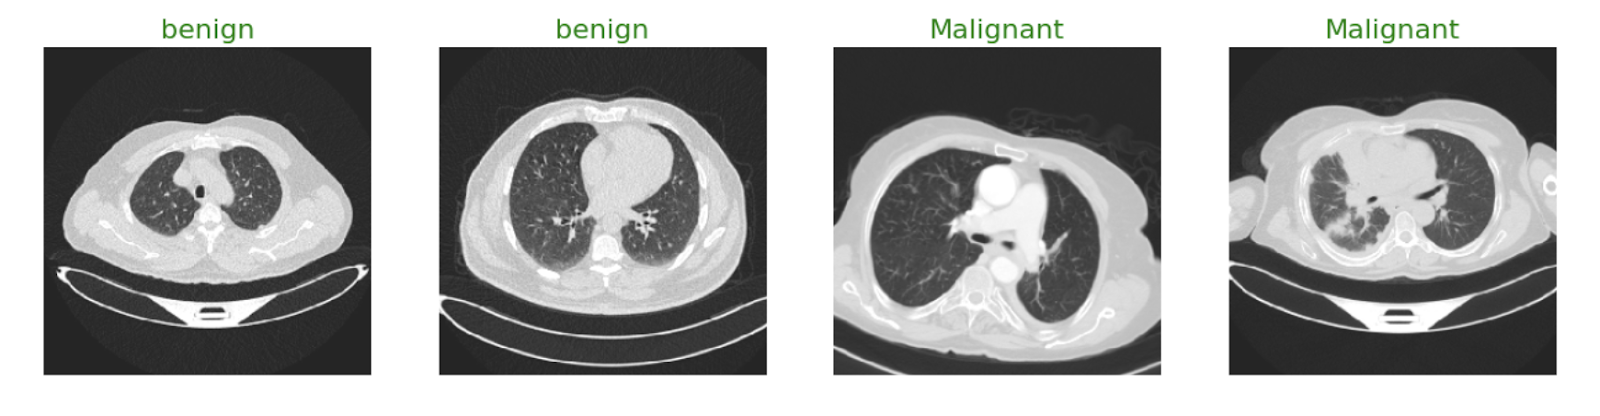

To test the power of federated learning, we built a lung cancer detection model using two open datasets:

We trained the same CNN model in three different collaborative scenarios to see how performance changed as more data sources joined the network. The CNN model and dataset details are available on the link mentioned above. The following results are based on the image dataset. If needed, one can use Tabular data with other models like SVM to reproduce similar results.